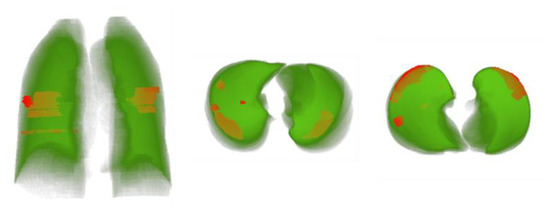

4.5. 3D Modeling of Lung Volume with Lesion Visualization